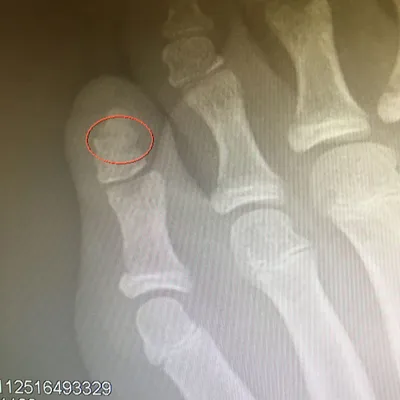

Below is an x-ray image of an extra-articular fracture of the proximal phalanx of the hallux (great toe) of a child. the fracture line does not enter the joint.